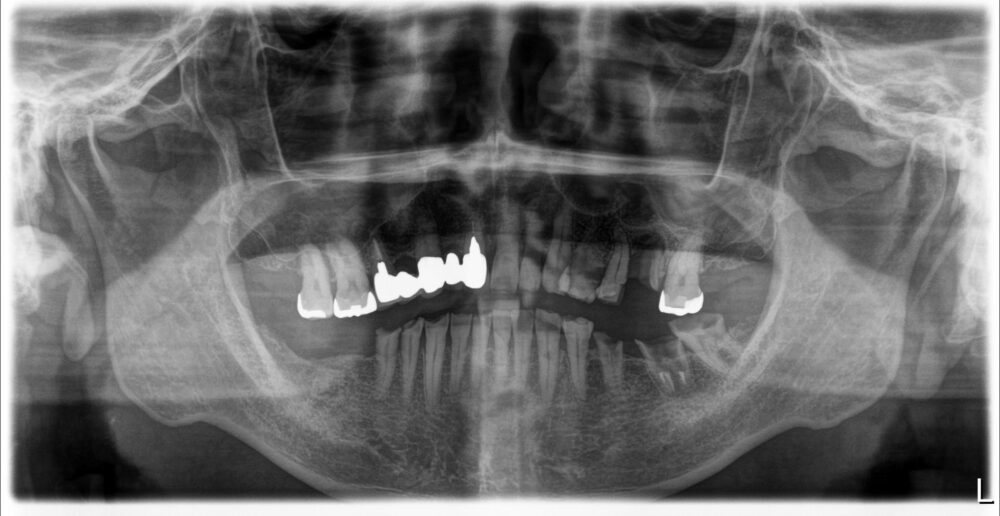

症例2

治療前

| 主訴 | 左上奥歯痛い |

|---|---|

| 診断 |

左上6歯根破折 |

| 治療内容 | 左上6インプラント抜歯即時埋入 |

| 年齢・性別 |

66歳、女性 |

| 治療期間 |

6ヶ月 |

| 治療費用 | 診査診断¥22000+一次オペ(アストラ)¥330000+GBR¥110000+¥上部構造¥143000 合計¥605000 |

| リスク・副作用 | インプラント周囲炎、上部構造の緩み |